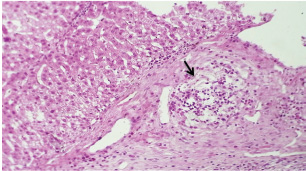

Histopathological examination of rabbits infected with T. annulata (G2) demonstrated progressive pathological alterations in various organs, in contrast to the control group (G1), which exhibited no abnormalities. At 14 days of post-infection, the lungs exhibited moderate alveolar thickening, hyperemia, and the presence of developed schizonts, indicating early tissue involvement (Fig. 4). The liver showed multiple necrotic areas, extensive venous congestion, and parasitized red blood cells, suggesting severe hepatic distress (Fig. 5). The spleen exhibited scattered macrophages containing microschizonts and hemosiderin-laden macrophages, reflecting both immune activation and erythrocyte breakdown (Fig. 6). The kidneys were affected by tubular infiltration with parasitized mononuclear cells (MNCs) (Fig. 7), whereas the mesenteric lymph nodes showed marked architectural disruption and merozoite aggregation (Fig. 8), suggesting significant immune system involvement.

At 21 days post-infection, the lungs display moderate venous dilation and congestion, with abnormal leukocytes, indicating ongoing vascular compromise (Fig. 9). The liver showed necrotic changes in the fibrous capsule region, focal inflammatory cell infiltration, and intact hepatic cords, indicating sustained but localized damage (Fig. 10). The spleen exhibited plasma cell and macrophage proliferation within the red pulp, mild sinus dilation, and a few megakaryocytes, suggesting chronic immune activation (Fig. 11). The kidneys showed atrophic glomerular tufts and cystic dilation of adjacent tubules, indicating worsening renal pathology (Fig. 12). The mesenteric lymph nodes showed lymphoid follicles containing abnormal plasma cells and macrophages within the necrotic foci (Fig. 13).

Fig. 7. A histopathological section of kidney of (G2) at 14 days postinfection showing tubular infiltration with parasitized mononuclear cells (black arrow) (H&E stain X 40).

Fig. 9. A histopathological section of lung of (G2) at 21 days postinfection showing moderate venus dilation and congestion with number of abnormal leukocytes (black arrow) (H&E stain X 40).